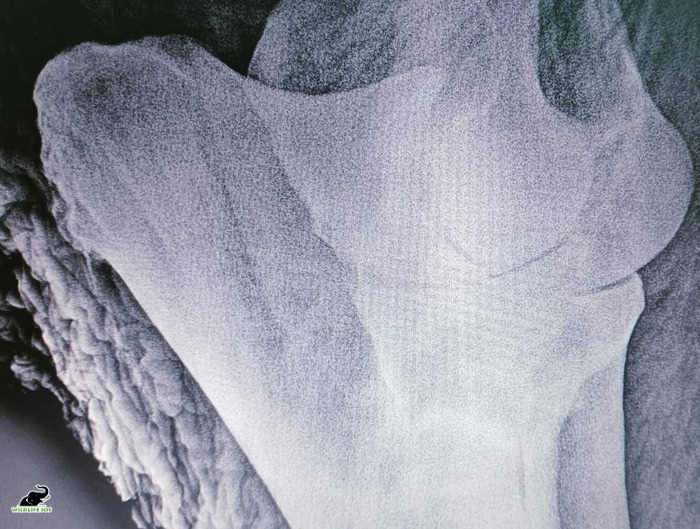

Improvement in his appetite was reflected in his consumption of 50 kg of fodder, 8 kg of fruits and vegetables, and 45 litres of water over a day. His bowel movement is healthy. X-ray results revealed degenerative joint disease and hairline fractures.

- The x-rays revealed inflammation lesion (osteitis) on edges of the bone due to long term malnourishment. [Photo © Wildlife SOS]